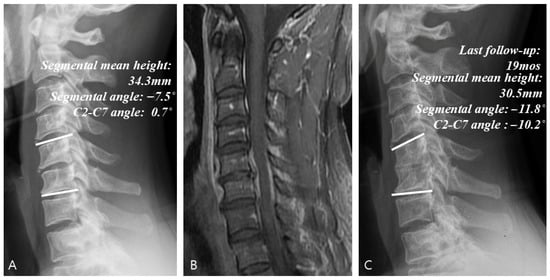

| Segmental angle (°) | |||||

| -First visit | −2.7 ± 3.1 | −2.4 ± 5.9 | −2.7 ± 4.7 | 1.000 * | (−1.2, 1.5) |

| -Last follow-up | −3.1 ± 3.8 | 2.7 ± 5.4 | −2.8 ± 4.6 | <0.001 * | (2.8, 9.2) |

| p-value a | 0.724 ^ | <0.001 ^ | 0.981 ^ | ||

| C2-C7 angle (°) | |||||

| -First visit | 8.4 ± 8.1 | 8.2 ± 7.8 | 9.4 ± 6.0 | 0.797 * | (−2.1, 2.5) |

| -Last follow-up | 8.1 ± 6.8 | 16.7 ± 8.4 | 9.1 ± 7.3 | 0.001 * | (3.2, 13.8) |

| p-value a | 0.859 ^ | <0.001 ^ | 0.744 ^ | ||

| Mean height change (%) | −19.3 ± 11.9 | 14.0 ± 15.8 | −7.8 ± 10.9 | <0.001 * | (18.5, 42.3) |

| Fusion achievement | 2/14 | 27/32 | 6/13 | <0.001 ‡ | (28.4%, 80.2%) |